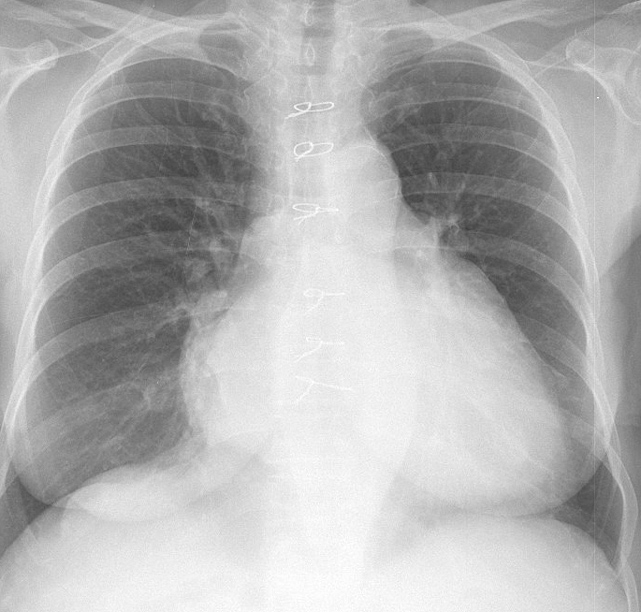

Gallery Cardiac Mitral Valve Disease Mitral Valve Disease Case 7 PA

Mitral Valve Disease

Case 7 PA